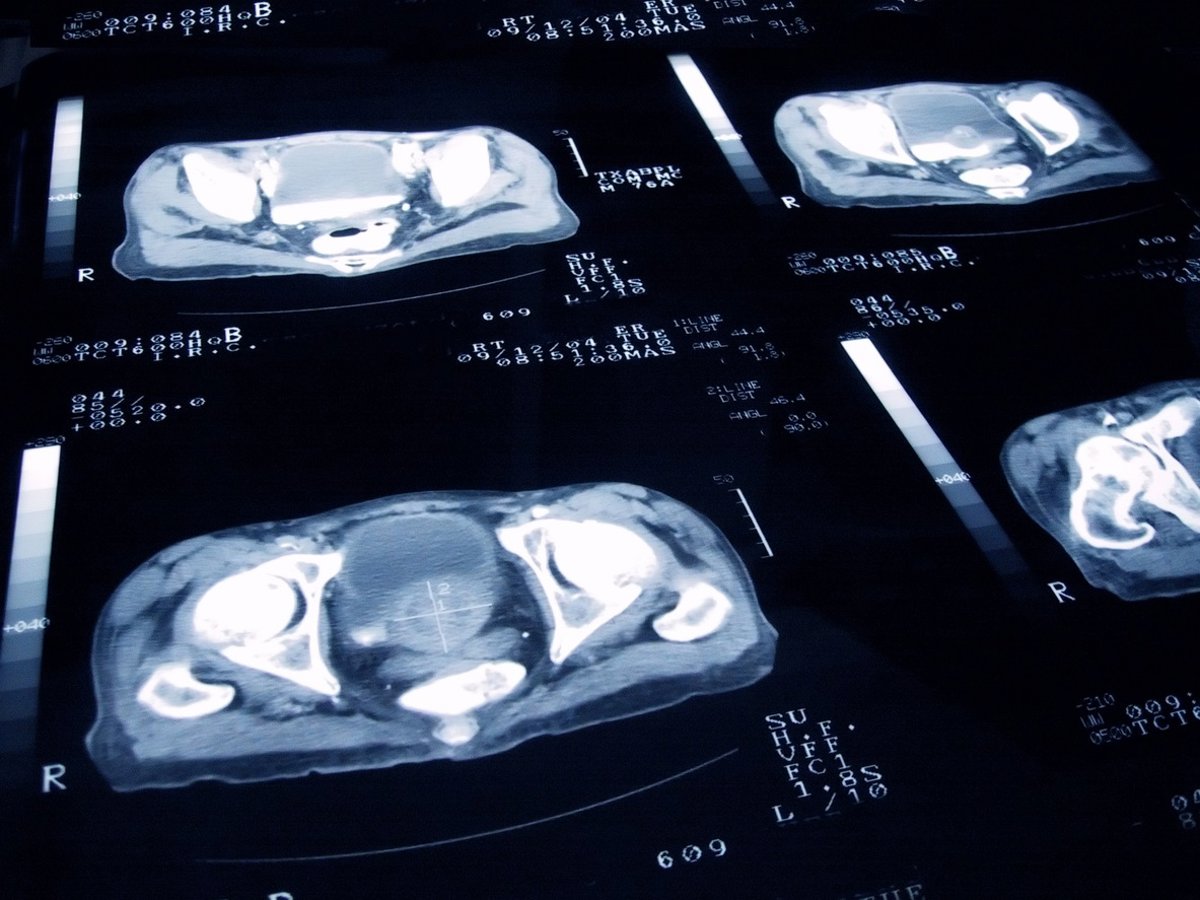

Archivo - Imagen de recurso de una próstata.

Archivo - Imagen de recurso de una próstata. - JAMESBENET/ ISTOCK - Archivo